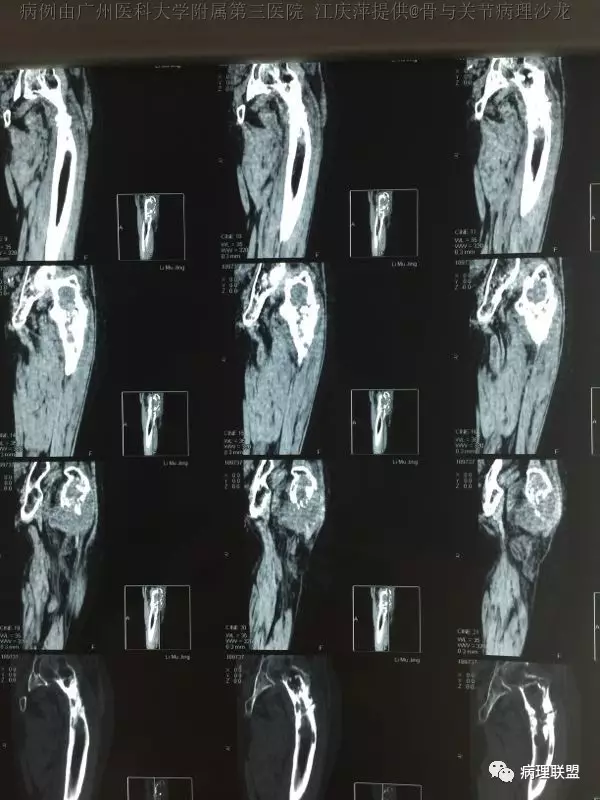

女,63,反复髋关节疼痛30年,活动受限2周(病例由广州医科大学附属第三医院 江庆萍提供,致谢)